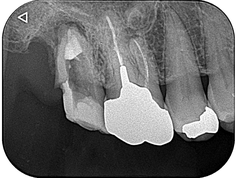

ファイバーコアにて支台築造して経過観察していましたが、根管充填後6週目で歯肉の著しい腫脹を認めたため、歯根端切除術を併用した意図的再植術に切り替えました。歯根の離開度が大きいと適応できない場合があるため、今回のように癒着していると抜歯が非常に楽です。

3週間後の経過観察で無事に生着していることを確認しました。歯肉の炎症も消失し、良好な経過と判断したため歯冠修復に移行しました。

8か月後の経過観察になります。根尖部の透過像は大幅に縮小していることが確認できます。患者さんの自覚症状もなく、良好に経過しております。抜歯しなくて大丈夫だったことを大変喜ばれておりました。